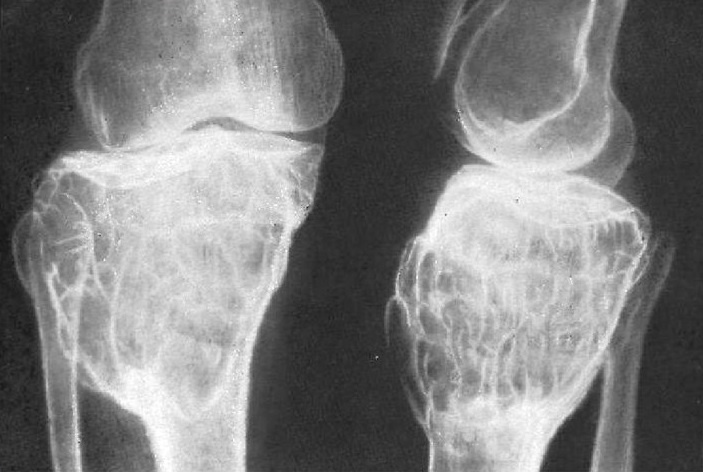

1. Рентгенография: Первое исследование для визуализации костной структуры.